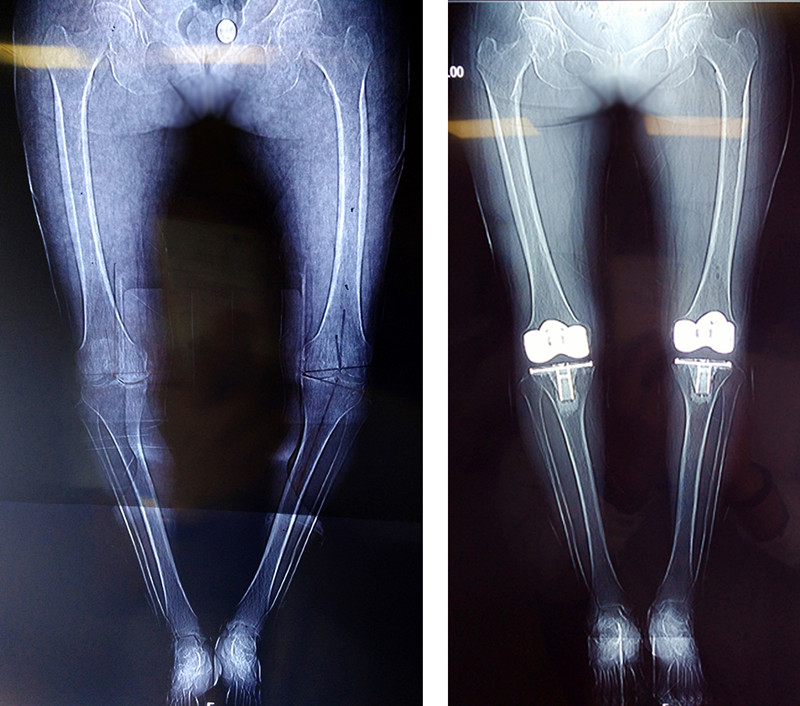

图为徐大娘下肢全长术前术后X光片对照

“这病得有30多年,但这几年实在疼得受不了了,做饭都得坐着,钻心的疼痛就像锥子刺在身上一样,有时真是觉得不想活了……”一个多月以前,徐大娘由老伴陪着来到市中心医院骨关节外科,看到李怡飞副主任,充满期待。看了片子,李主任皱了下眉头说,这是膝关节骨性关节炎晚期,双侧膝关节内翻畸形已经快30°、屈曲畸形约10°,双膝关节内侧间隙基本消失,骨赘增生明显,可能需要做膝关节置换手术了。

经过详细讨论,专家们为她制定了缜密的手术方案。为减少患者手术费用,大家决定为徐大娘同时实施双侧膝关节置换;为了减少输血带来的风险,预备了术中自体血回输装置;同时还准备了充分的手术预案,特意准备了更高级的限制性人工关节。手术当天,徐大娘完成了全身麻醉,手术有条不紊的开始进行。李怡飞副主任和他的手术团队全都紧绷神经,不敢有一丝松懈。无论是截骨矫形还是安装假体都异常小心,犹如对待一件易碎的珍品。3个小时后双侧膝关节同时置换手术成功完成,这时,李怡飞才意识到自己的后背早已被汗水打湿。